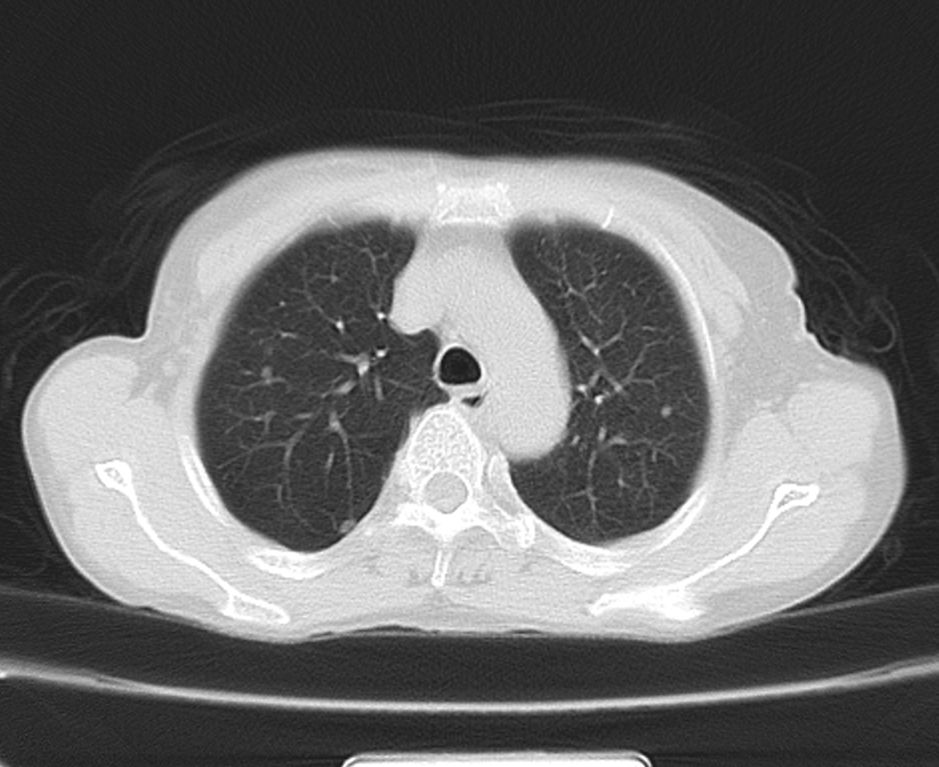

标题: CT21609:右乳包块1年,请各位讨论分析一下,乳腺CA, [打印本页]

标题: CT21609:右乳包块1年,请各位讨论分析一下,乳腺CA,

考虑---右乳癌并胸壁、肋骨、双肺转移。

考虑乳腺癌侵犯肋骨、胸壁及两肺转移可能性大。

右乳癌并胸壁、肋骨、双肺转移。

考虑右侧乳腺癌侵犯肋骨、胸壁及两肺转移。

支持考虑---右乳癌并胸壁、肋骨、双肺转移。

考虑右侧乳腺癌侵犯肋骨、胸壁及两肺转移可能。

考虑右侧乳癌并胸壁、肋骨及双肺多发性转移。